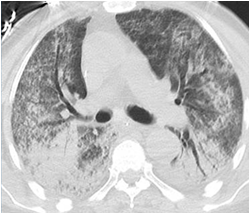

• 胸部CT:2020年10月9日胸部CT示双肺多发渗出高密度实变阴影(图1)

1  胸部CT:双肺多发渗出高密度阴影(2020年10月9日)